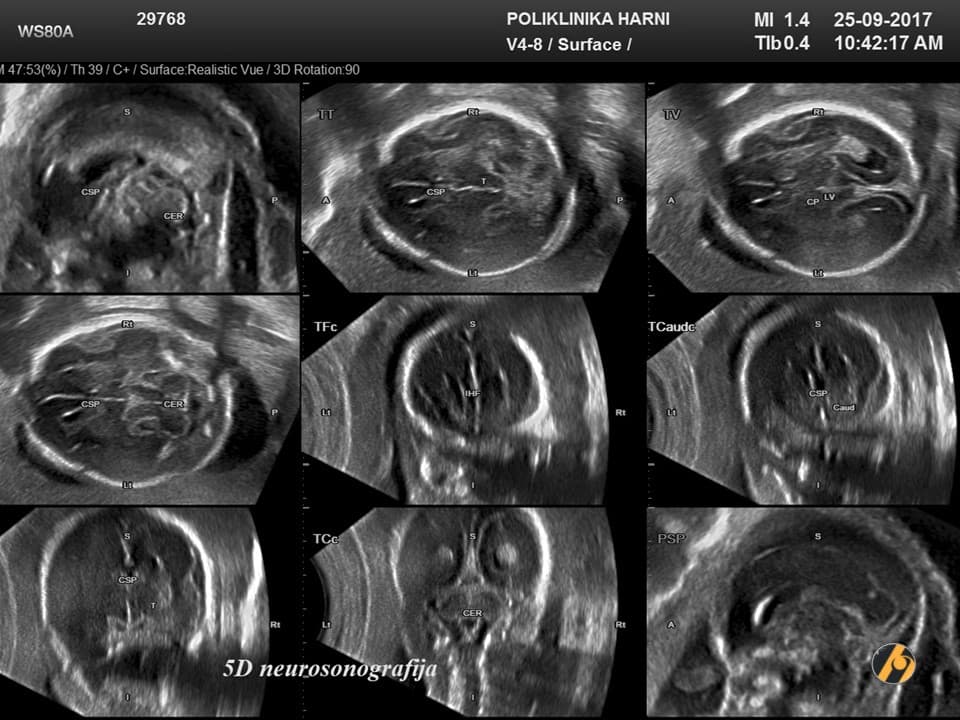

Ovaj pregled omogućuje liječniku da procijeni razvija li se beba uredno te pruža važan uvid u tijek trudnoće, kao i da preporuči dodatne pretrage kao što su fetalna neurosonografija ili fetalna ehokardiografija.